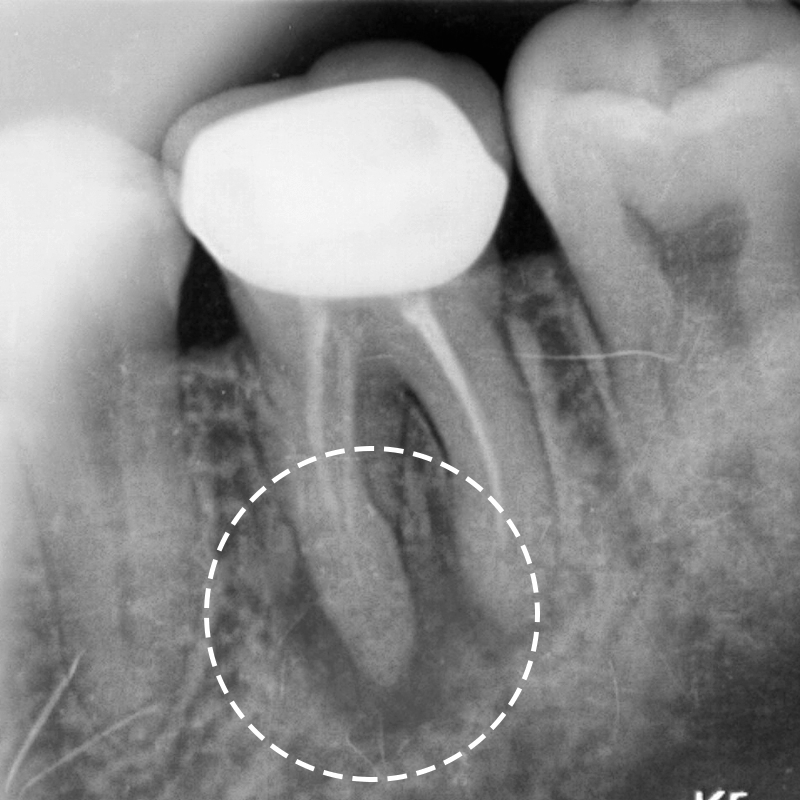

우선 잇몸 안쪽에 어떠한 문제가 생겼을 경우 외부의 색 변화나 통증이 느껴질 정도라면 이미 안쪽에서 염증이 많이 발생하였고 꼭 치료를 해야한다고 할 수 있겠어요. 보시는 것과 마찬가지로 잇몸에 염증으로 가득차서 튀어나와 있는 모습을 확인하실 수 있을텐데요. 이렇게 육안으로 보일 정도로 티가 나게 될때 까지 방치한 경우에는 한시라도 빨리 병원에 내원하시는 것이 좋습니다. 우선적으로 잇몸이 부었을 때에는 휴식을 취하거나 몸의 컨디션을 회복하면 금방 잇몸에고름이 가라앉기도 하였지만, 이런 상황이 반복되거나 쉽게 가라앉지 않고 고름이 커지거나 터지는 경우, 심지어 피가 나는 경우에는 그냥 내버려 두면 쉽게 가라앉지 않고 염증을 더 키워 나중에는 치료할 때에 더 애를 먹었었는데요. 그러다 보니 잇몸에 이러한 고름이 생기는 원인을 정확하게 파악해서 그에 맞는 치료를 제대로 받는 것이 재발을 방지하고 건강한 치아와 잇몸을 유지하는 데 도움이 되었었어요.

치주낭종이라 불린다는 잇몸고름주머니는 치아 신경조직이 세균에 감염되면서 치아 뿌리에 생긴 염증이 잇몸뼈를 뚫고 튀어나오는 현상이었는데요. 여기서 낭종이란 액체나 반고체의 물질이 들어 있는 주머니 모양의 혹으로 몸 어디든지 생길 수 있는 것인데 잇몸염증이 생겨 치아에 생겨난 낭종인 것이었지요. 주변의 조직보다 높은 삼투압에 의해 조직 사이의 액이 모이고 모여서 커지게 되는 것이었어요. 대부분 이 뿌리 끝 염증 속 고름은 빠져나오다 보니 생기더라도 통증이 없어 칫솔질을 하거나 혀로 잇몸을 건들 때 발견하곤 하였는데요. 이런 고름이 통로가 막혀 나오지 못하는 경우 통증이 생기고 내버려 두는 경우 냄새는 물론 이가 시리거나 악화하면 이가 흔들리고 음식을 씹을 때조차 통증으로 음식 섭취를 하는 그것조차 힘들게 되는 경우가 있었어요.

잇몸고름주머니가 생기는 원인은 충치인 경우가 일반적이었는데요. 충치가 심해지면 치수 조직까지 염증이 퍼지게 되고, 치수 조직이 괴사하고 치아 뿌리까지 염증이 생기게 되어 잇몸염증이 점점 커지면서 잇몸뼈를 뚫고 나오면서 생기는 것이었어요. 또 다른 원인은 충치 수복 물이 신경을 계속 자극하면서 치수 조직이 괴사하는 경우였는데요. 세균 감염이 일어나 치아 뿌리에 염증을 일으켜 치아낭종으로 이어지는 것이었어요. 그리고 치주질환이나 매복 사랑니에 의해서도 생길 수 있었는데요. 이때 주머니안의 고름을 없애주기만 해도 해결이 가능하기도 하였지만 매복 사랑니의 경우에는 통증이 발생하는 경우가 대부분이라 염증을 가라앉힌 후에 발치하여 윗몸고름주머니치료를 하기도 하였었어요. 또한 치과에서 흔히 치료를 하는 신경치료도 원인이 될 수 있었는데요. 신경치료가 제대로 진행되지 않아 치아의 신경 속에 세균이 침투하여 다시 감염이 일어나 치아 뿌리에 염증을 일으켜 잇몸에고름이 발생하는 것이었지요. 더불어 신경치료를 받았었는데 재발하거나, 신경이 죽어서 치아 뿌리쪽에 염증이 생겨 잇몸에 고름이 차오르는 경우도 있었어요.

과거에 씌운 치아 또는 신경 치료했던 치아 뿌리 끝쪽에서 발생한 염증은 신경관 내의 감염을 막기 위해 세균을 없애야 했는데요. 씌운 치아라면 이것을 제거하고 신경치료를 진행하거나 이미 신경치료를 받았던 치아라면 재신경치료를 할 수 있었는데요. 이런 경우 기존에 씌운 크라운을 제거한 후에 신경관에 채워져 있는 충전재를 제거하고 오염 부위를 치아 염증 조직을 깨끗하게 제거하고 소독과 세척을 진행한 후에 새로운 충전재로 빈틈없이 밀봉한 후 새로운 크라운으로 수복하여 치료하였었는데요. 신경치료를 다시 하는 것은 기존 신경치료보다 까다롭고 어렵다 보니 양질의 진료를 받을 수 있는 곳이 필요했었는데요. 최신 트랜드와 치료방법, 첨단장비 등은 물론 전문 의료진의 풍부하고 더 많은 시술 경험과 노련함이 적절한 치료를 받는 기준에서 무엇보다 가장 중요한 것이었었어요.